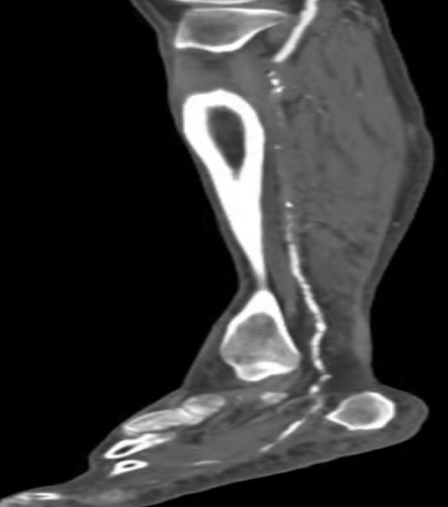

下肢動脈CTA